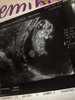

Dziewczyny jestem po wizycie, u dzidzi wszystko dobrze, ma niespelna 3cm i bardzo wariuje w brzuszki. Macha nóżkami i rączkami ciągle. Super to wyglądało az sie wzruszylam. Niestety ta moja tarczyca do dupy, lekarz wyslal mnie do endokrynologa po Euthurox. Myslalan ze 3,34 to norma ale podobno teraz normy sie zmienily i musze brać leki. No ale trudno, byle po ciąży wszystko wrocilo do normy. Pokazuje zdjecie mojej szalonej kluseczki

• 26828492_1725662860828705_469210020_o.jpg